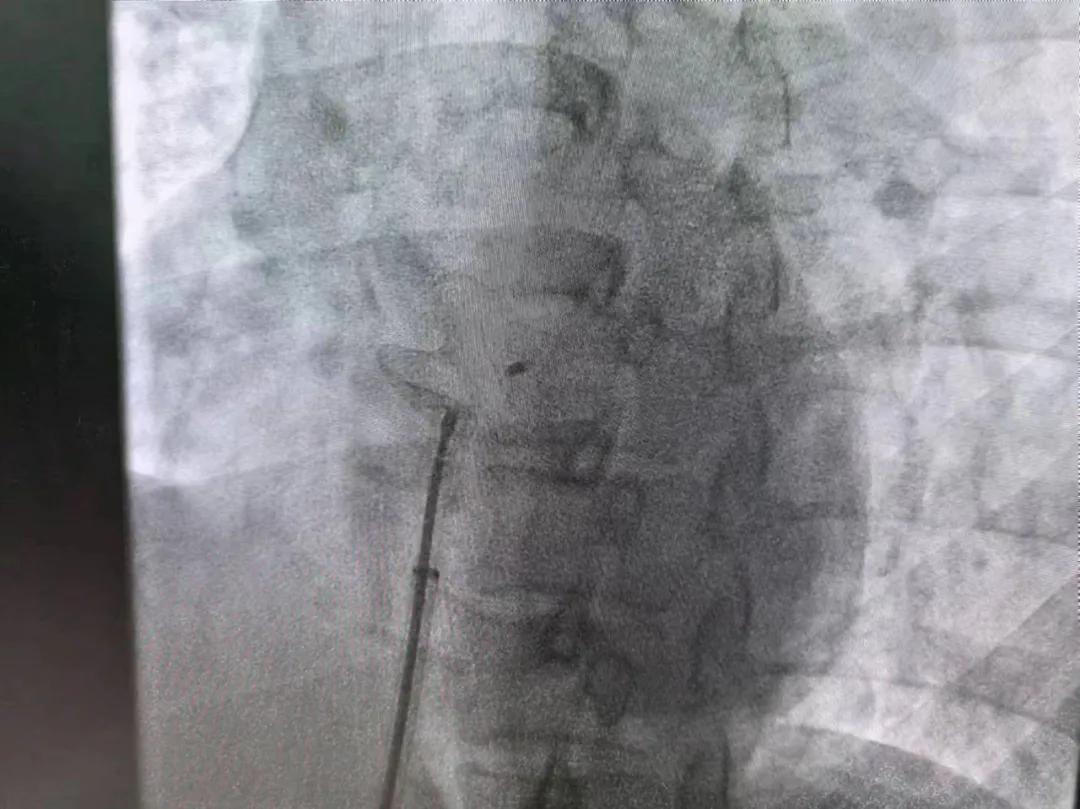

繼3月14日市二院成功開展首例卵圓孔未閉介入封堵術(shù)之后,3月21日上午,市二院院長王瑾及心血管內(nèi)科主任李慧新帶領(lǐng)心血管內(nèi)科介入團隊,再次成功為患者實施“經(jīng)皮房間隔缺損封堵術(shù)”,手術(shù)過程順利。該例病人的成功手術(shù)及康復(fù),標(biāo)志著市二院心血管內(nèi)科在結(jié)構(gòu)性心臟病介入診療中再次達到了新高度。

患者為中年女性,41歲,近2年一直反復(fù)出現(xiàn)頭暈、頭痛,曾先后在多家醫(yī)院就診。近期患者癥狀加重,出現(xiàn)活動后氣喘合并胸悶癥狀,來到心血管內(nèi)科就診。經(jīng)心臟彩超檢查顯示:患者房間隔下段連續(xù)性中斷,缺損直徑達到了13mm,肺動脈壓已經(jīng)輕度增高,確診為房間隔缺損。

于是,院長王瑾會診后,詳細詢問患者病史,認真分析臨床癥候群并準(zhǔn)確診斷,耐心做好患者及家屬病情告知和充分溝通。經(jīng)過完善的術(shù)前評估及準(zhǔn)備,心血管內(nèi)科介入團隊成功為患者實施“經(jīng)皮房間隔缺損封堵術(shù)”,手術(shù)過程順利。近日,患者已順利康復(fù)出院。 (尹紅婭 潘長林)